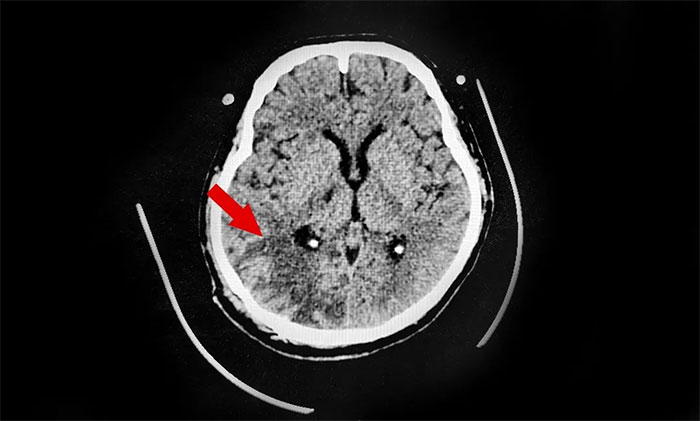

31歲的小王就是這樣的年輕腦出血患者,入院診斷:腦出血、肺部感染、尿路感染、肝功能不全、低纖維蛋白原血癥。神志淺昏迷狀態,肢體活動障礙。家人介紹,小王工作繁忙,生活不規律,體重超標,並且還是一杆“老煙槍”,幾乎每天一包煙,兩個月前突發腦出血倒下。

▲ 右側枕頂葉出血